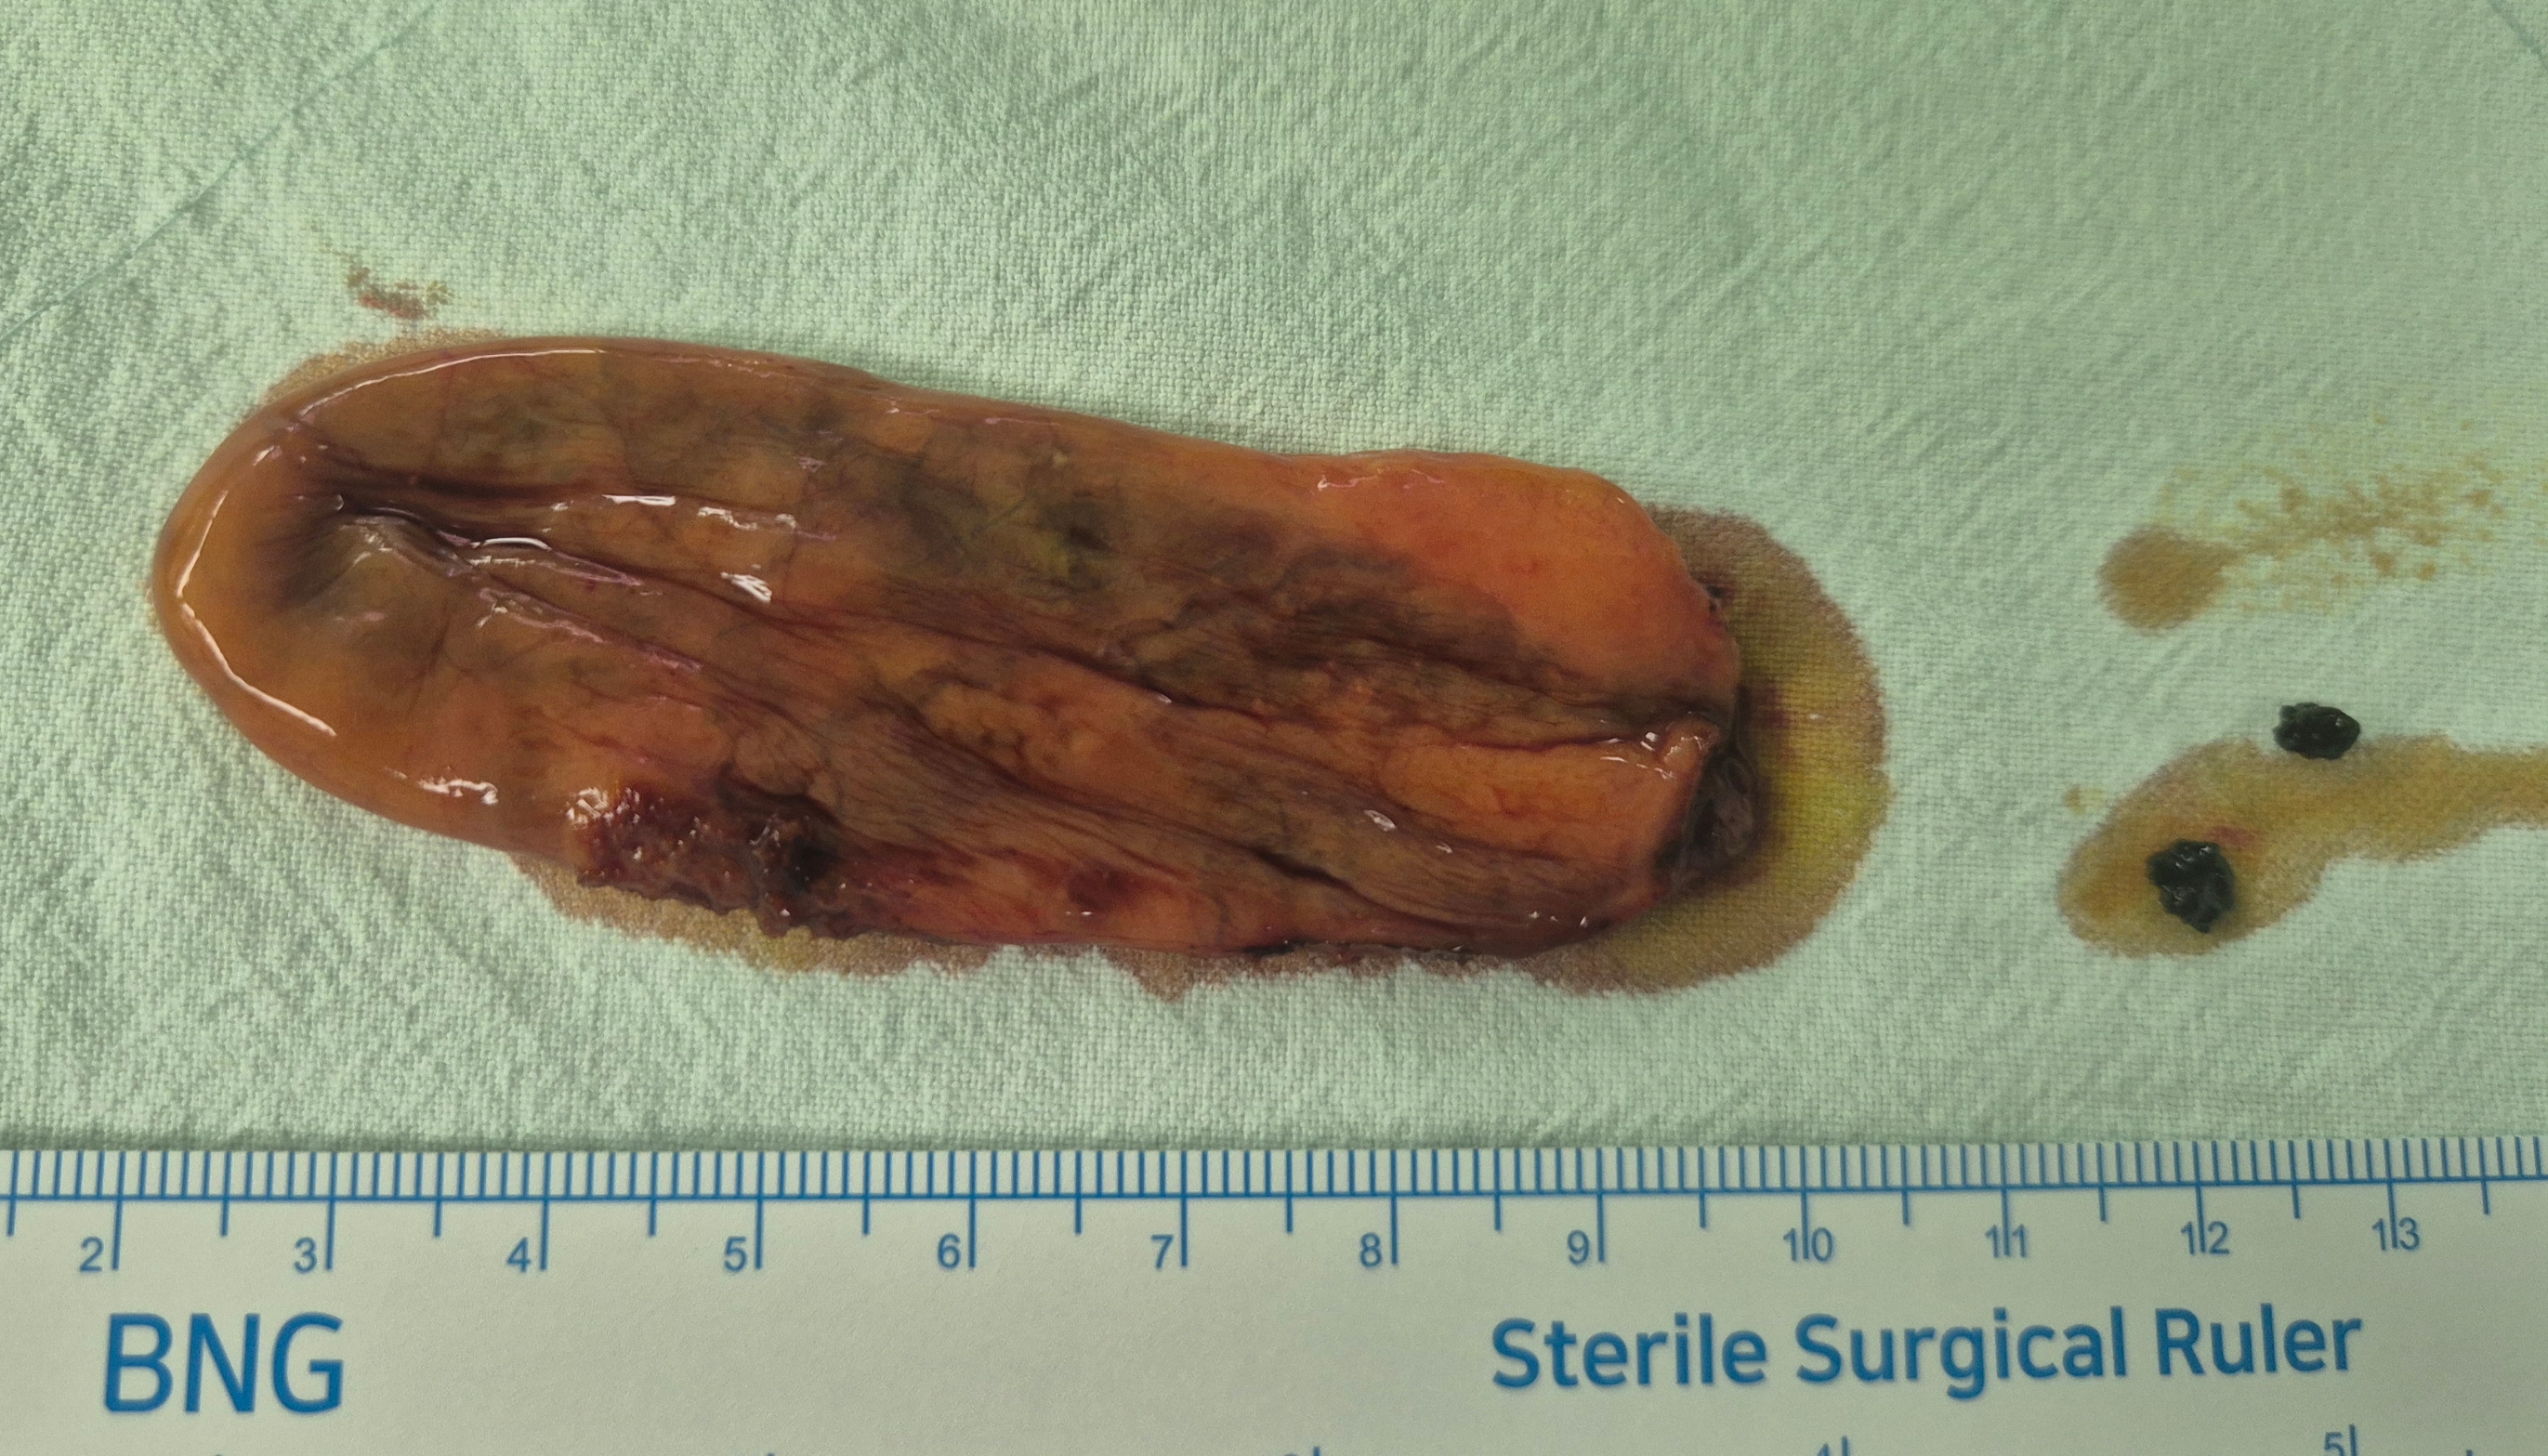

담낭용종 1.1cm 으로 확인되어 수술위해 제 외래로 오셨던 분입니다.

단일공 복강경 담낭절제술을 시행했습니다.

수술은 25분 걸렸습니다.